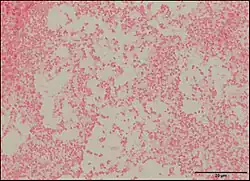

Pseudescherichia vulneris is a Gram-negative bacterial species. P. vulneris is a fermentative, oxidase-negative, motile rod, which holds characteristics of the family Enterobacteraceae. This bacterium can colonize in the respiratory tract, genital tract, stool, and urinary tract. However, P. vulneris is most often associated with wounds and has been known to colonize open wounds of both humans and animals. This association gave the bacterium its species name, vulneris, which is Latin for wound. It has also been infrequently reported in cases of meningitis. It was identified as Escherichia vulneris in 1982 with a 2017 genomic analysis of its original genus resulting in the creation of its new genus Pseudescherichia.[1][2]

Morphology

P. vulneris has a rod-like (bacilli) shape, and it achieves motility using peritrichous flagella (covering the whole body of the bacteria). P. vulneris is facultatively anaerobic, and is not spore-forming. Optimal growth occurs at 35-37 °C, and it can colonize on a simple nutrient medium. Colonies are generally smooth and low convex with shiny surfaces.[3]